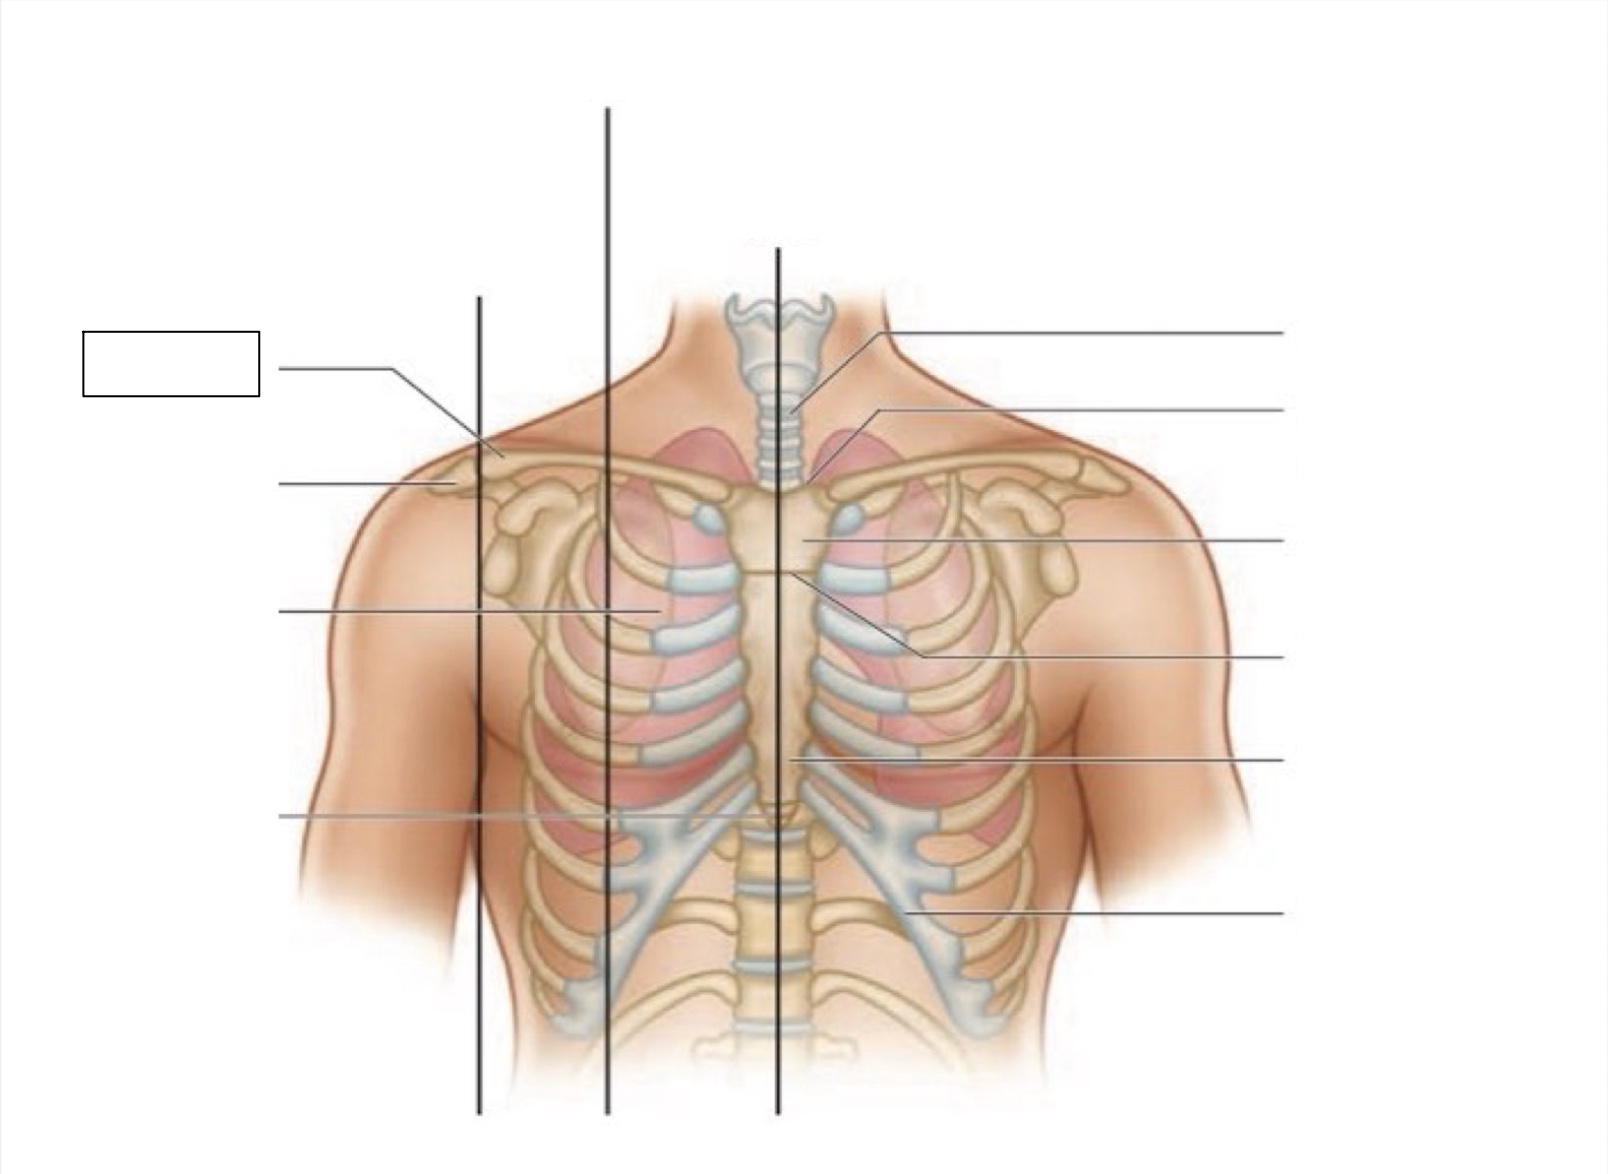

midsternal line

trachea

suprasternal notch

manubrium

angle of Louis

sternum

costal margin

xiphoid process

intercostal space

acromion

clavicle

anterior axillary line

midclavicular line

inferior angle of scapula

scapula

midscapular line

midspinal line

spinous process